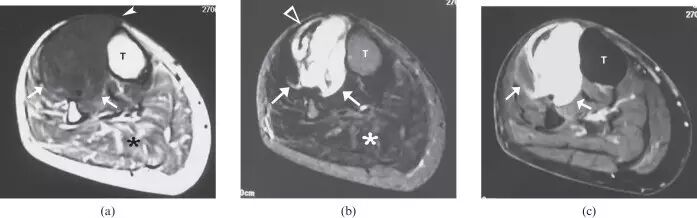

图25.一个67岁的男性结节型肌肉结节病,左大腿软组织包块,伴随腿疼痛。 (a)轴向T1加权磁共振图像显示在左腿的腓肠肌和胫骨前肌中的低信号强度结节(箭头)。 (b)轴向T2加权的MR图像显示由高信号强度(箭头)的厚边缘包围的中心低信号强度的肌内小腿损伤(箭头)。 ,在四头肌(箭头)中具有急剧的边缘状增强。 活检揭示非梗阻性肉芽肿。 T,胫骨。

![]()

图26.一名78岁女性的平滑肌肉瘤患者出现右腿疼痛,肿胀和无法行走。 (a)通过小腿的轴向T1加权的MR图像显示在胫骨前部和胫骨后肌中主要为低信号强度的大的、小叶的、清晰分界的团块损伤(箭头)。团块延伸到皮下组织(箭头)。由于身体活动减少,胫骨后隔室中的肌肉显示突出的脂肪浸润(星号)。 (b)具有脂肪抑制的轴向T2加权MR图像显示具有低信号(空心箭头)的外周坏死区域的主要高信号强度(箭头)的肌内病变。在该脂肪抑制图像上,比较在胫骨后部(星号)中的低信号强度,脂肪替代肌肉的外观与部分(a)中的脂肪替代肌肉的外观。 (c)具有脂肪抑制的轴向T1加权MR图像显示包块的不均匀增强(箭头)。包块病变的活组织检查提示胫骨肌肉的平滑肌肉瘤。 T,胫骨。